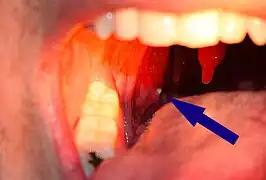

Un tonsilolito sobresale de la amígdala

Gran tonsilolito en amígdala izquierda